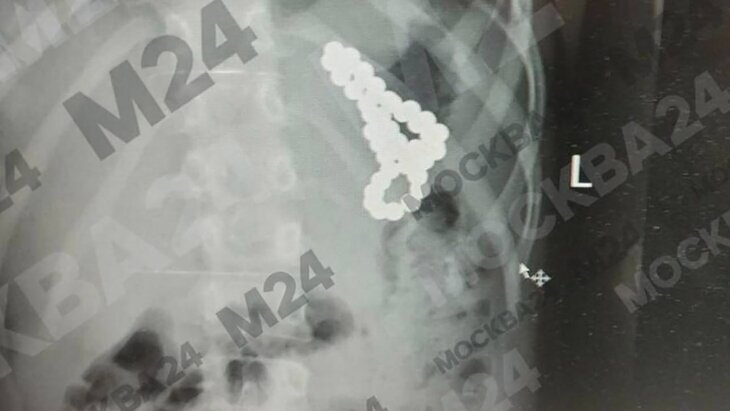

Специалисты Детской клинической больницы имени З. А. Башляевой провели успешную операцию по извлечению магнитных шариков из желудка восьмилетней школьницы. Об этом сообщает Москва 24 со ссылкой Депздрав столицы.

По итогам проведенного обследования врачи обнаружили 46 магнитных шариков в желудке ребенка. Медики приняли решение провести экстренную операцию. Им удалось вытащить все инородные предметы из тела девочки.